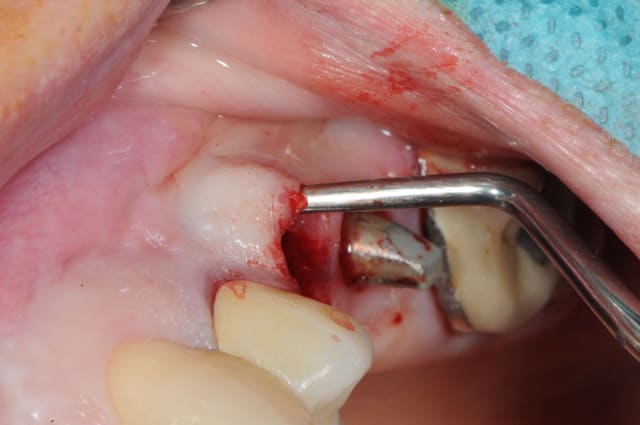

1- curette en appuie sur la face vestibulaire montrant la destruction osseuse.

2- lambeau pleine épaisseur en palatin pour aller chercher un bout de conjonctif qui soit pédiculé.

3 je décole à partit des rebords de la déhiscence osseuse et reste en contacte permanent avec la corticale osseuse tout en décollant la gencive (elle est soulevé donc)